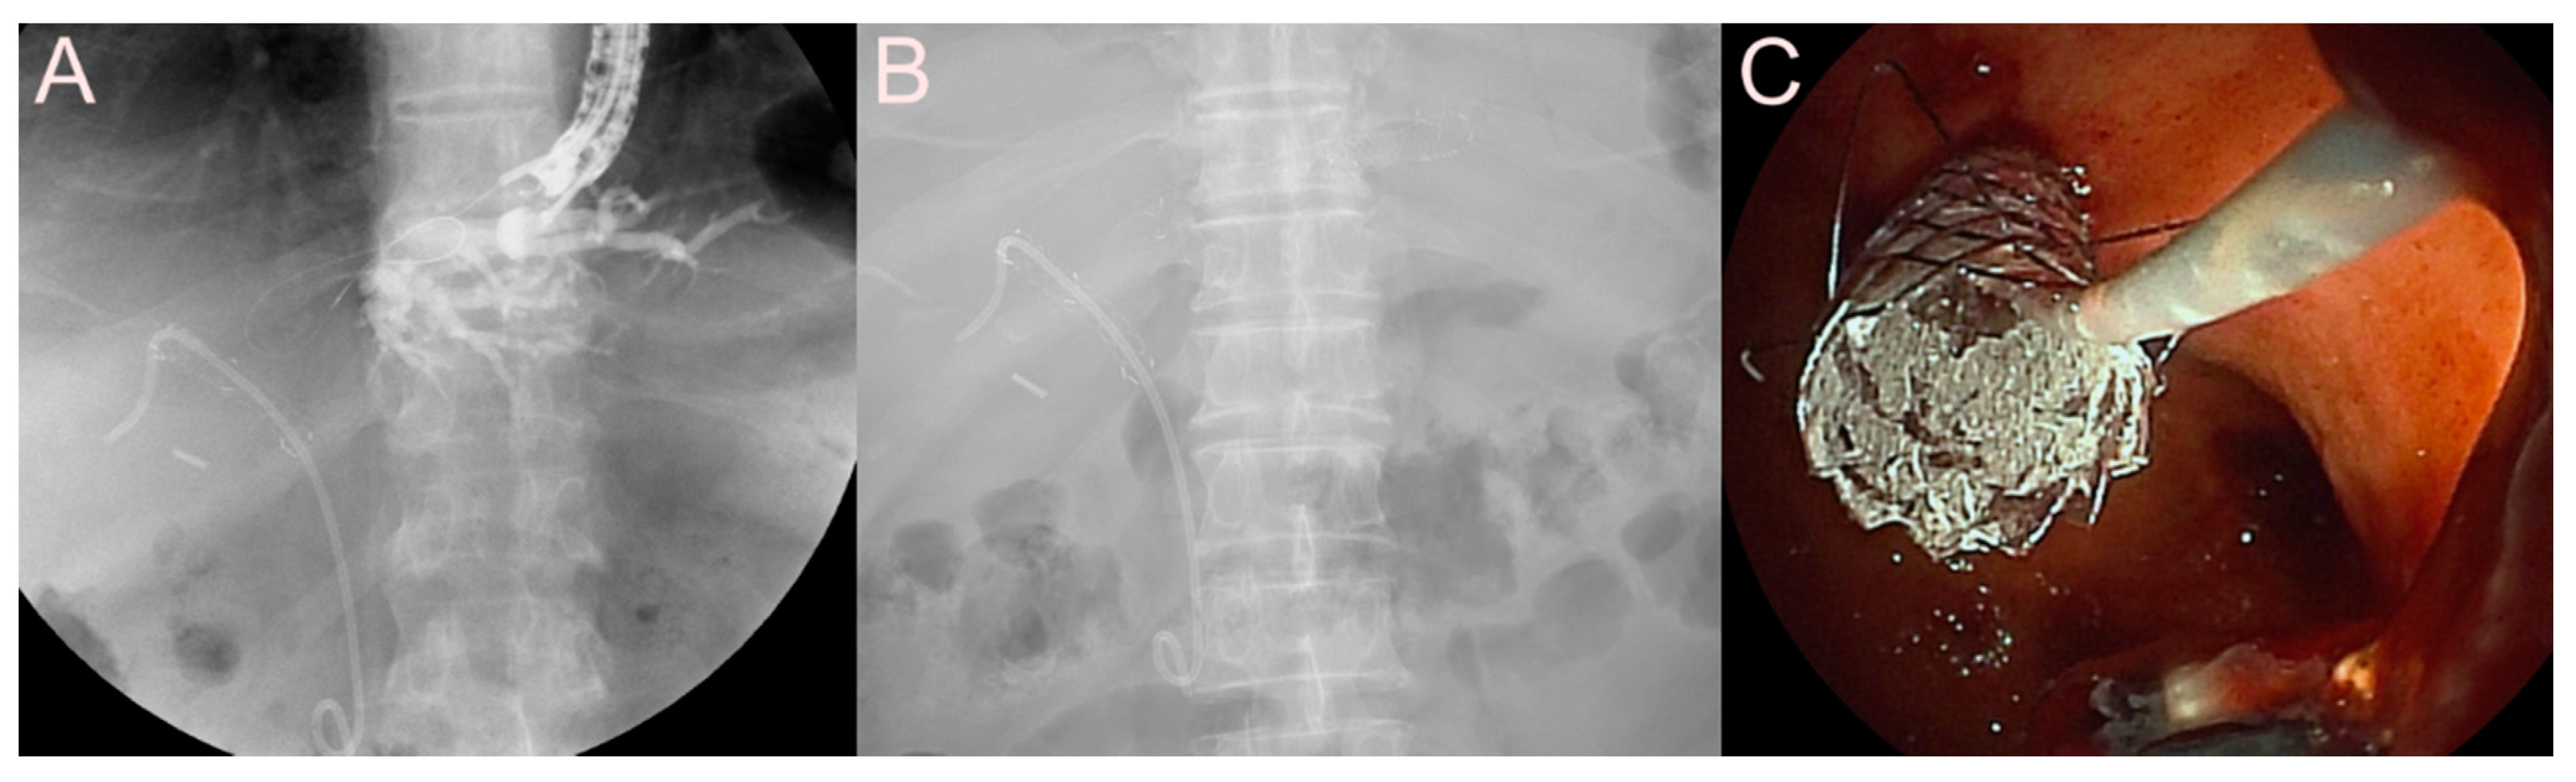

2.2.2. Use of the SEMS